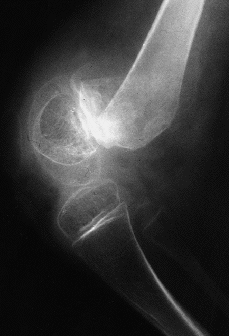

Figura 2. Ejemplo de una fractura epifisiolisis distal de fémur, consecuencia de la osteoporosis tras la cirugía y período de inmovilización, además del flexo de rodilla que se suele asociar en estos pacientes.